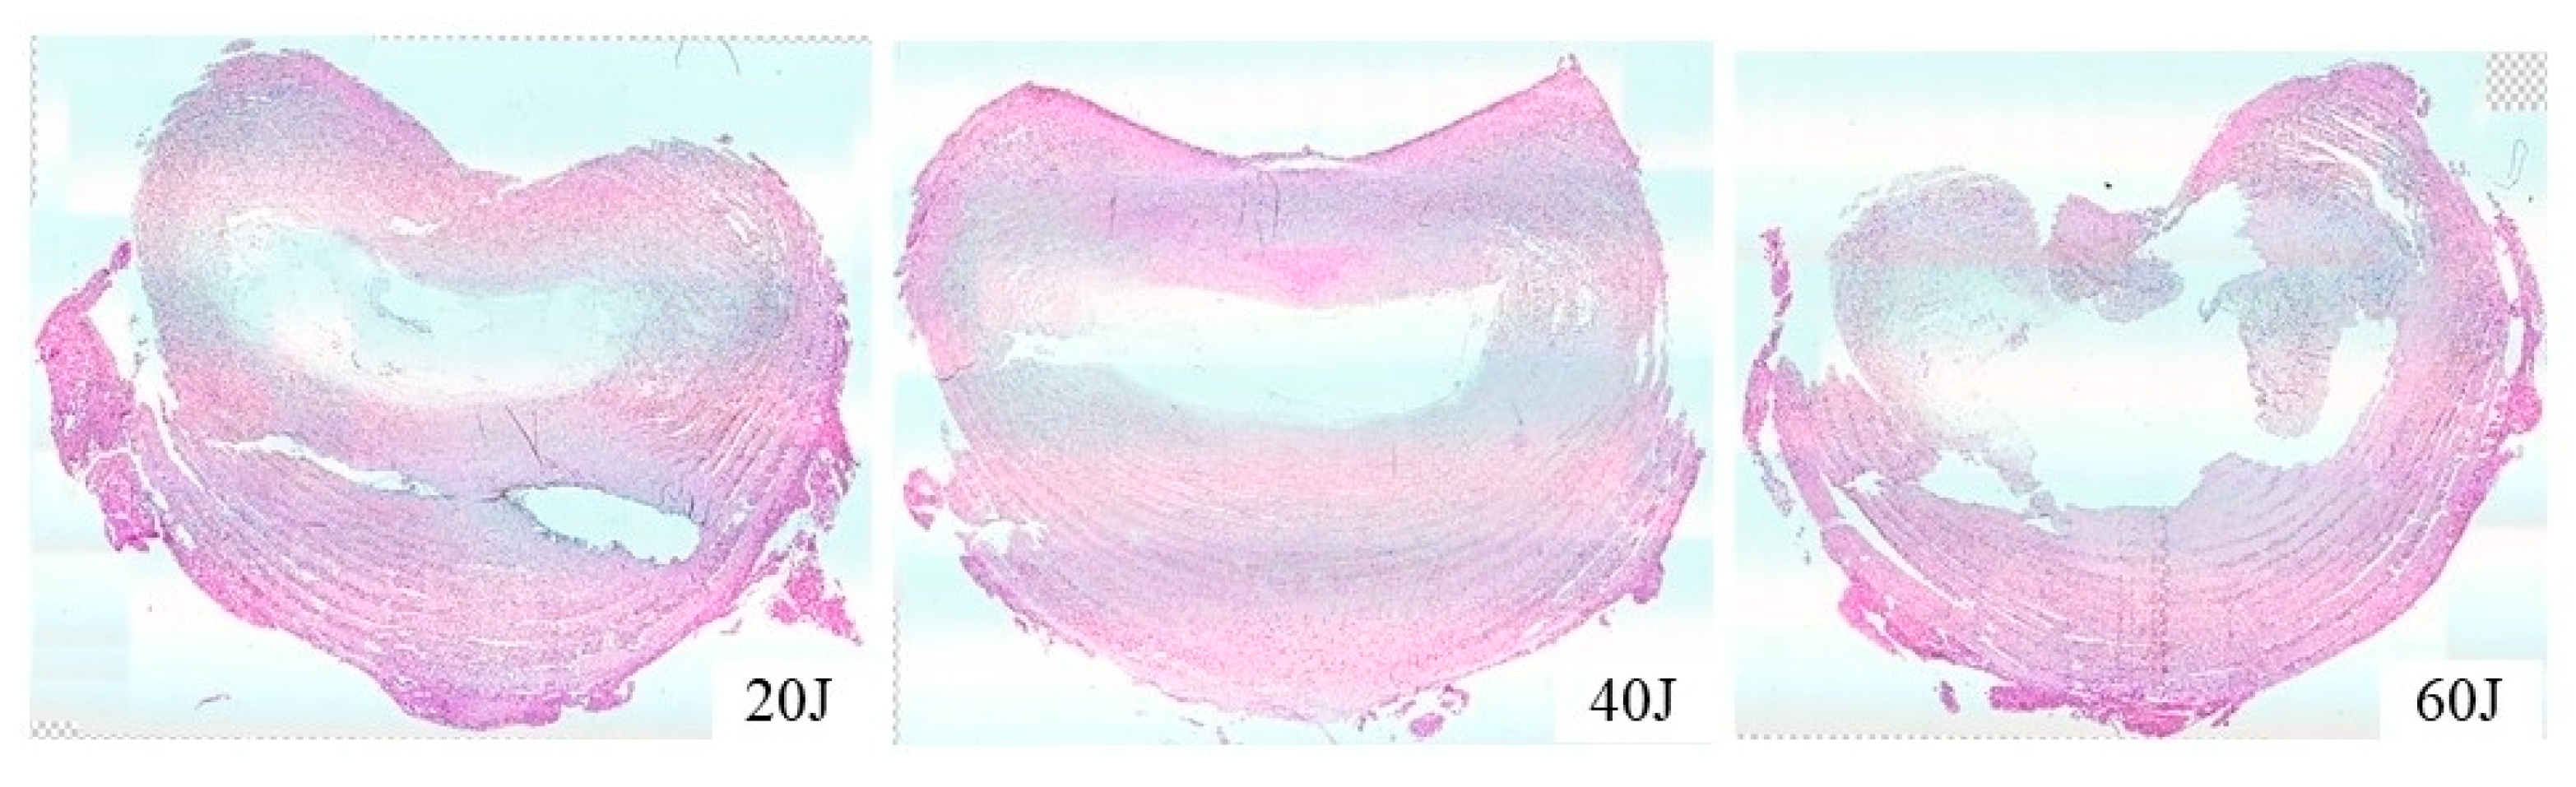

3.2. NP Changes after Laser Treatment

3.3. Vaporized NP Weight According to Total Energy